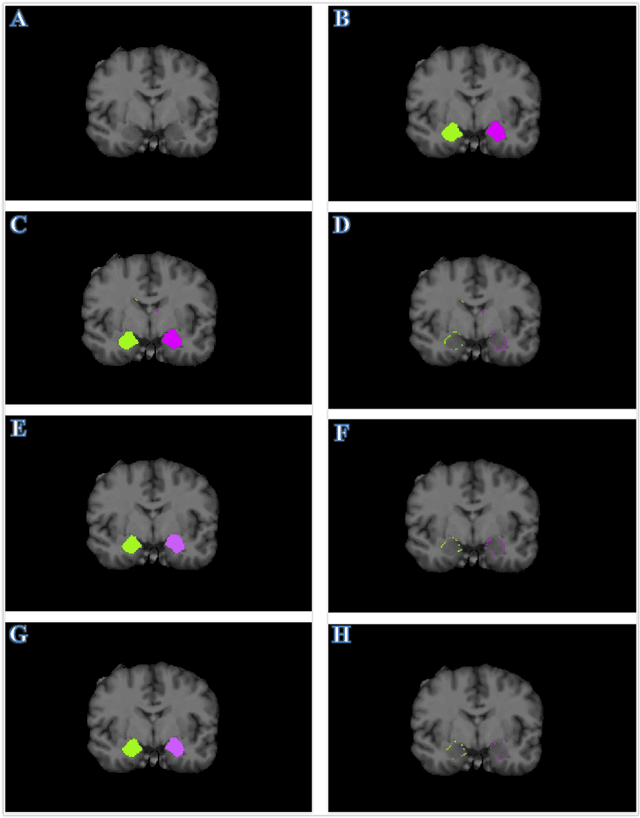

Abstract:Recent advances in deep learning have improved the segmentation accuracy of subcortical brain structures, which would be useful in neuroimaging studies of many neurological disorders. However, most of the previous deep learning work does not investigate the specific difficulties that exist in segmenting extremely small but important brain regions such as the amygdala and its subregions. To tackle this challenging task, a novel 3D Bayesian fully convolutional neural network was developed to apply a dilated dualpathway approach that retains fine details and utilizes both local and more global contextual information to automatically segment the amygdala and its subregions at high precision. The proposed method provides insights on network design and sampling strategy that target segmentations of small 3D structures. In particular, this study confirms that a large context, enabled by a large field of view, is beneficial for segmenting small objects; furthermore, precise contextual information enabled by dilated convolutions allows for better boundary localization, which is critical for examining the morphology of the structure. In addition, it is demonstrated that the uncertainty information estimated from our network may be leveraged to identify atypicality in data. Our method was compared with two state-of-the-art deep learning models and a traditional multi-atlas approach, and exhibited excellent performance as measured both by Dice overlap as well as average symmetric surface distance. To the best of our knowledge, this work is the first deep learning-based approach that targets the subregions of the amygdala.